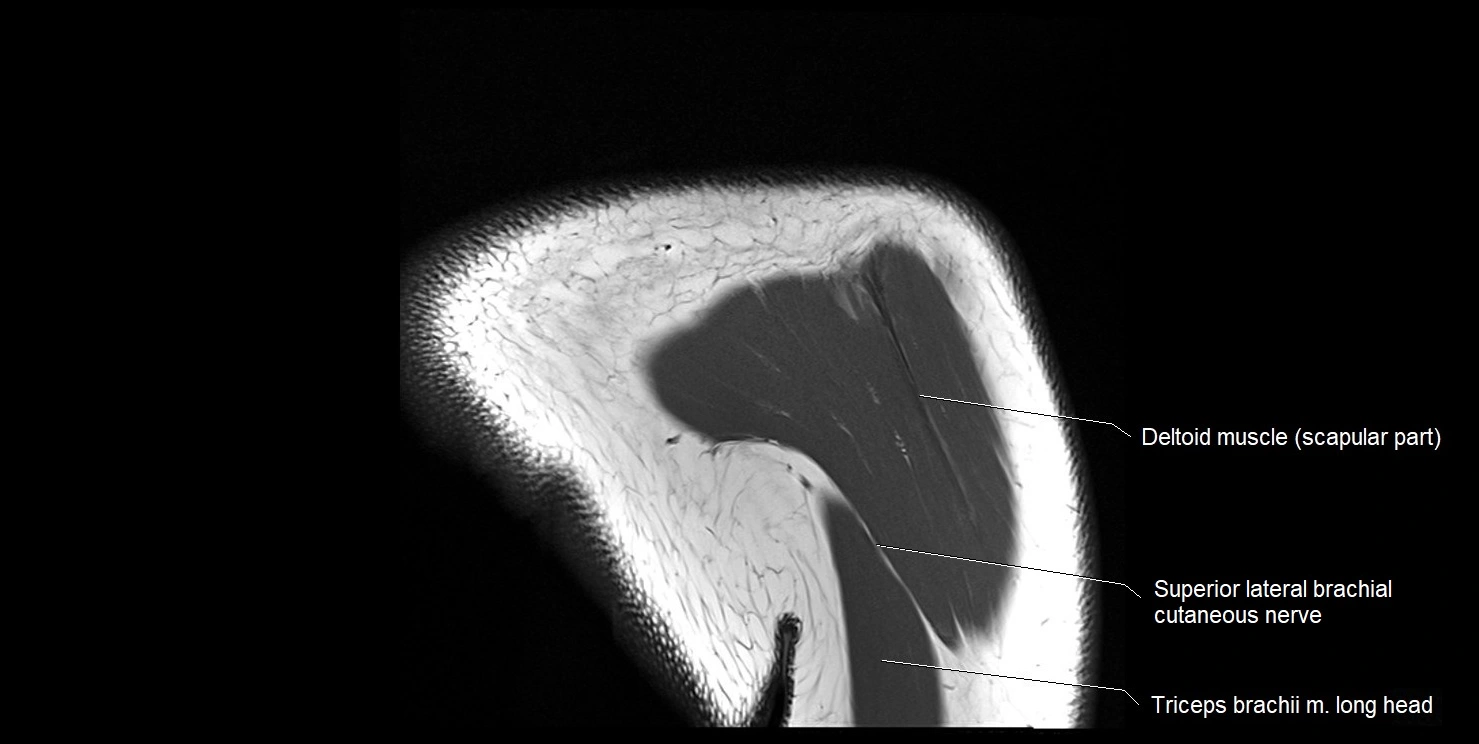

MRI images

image